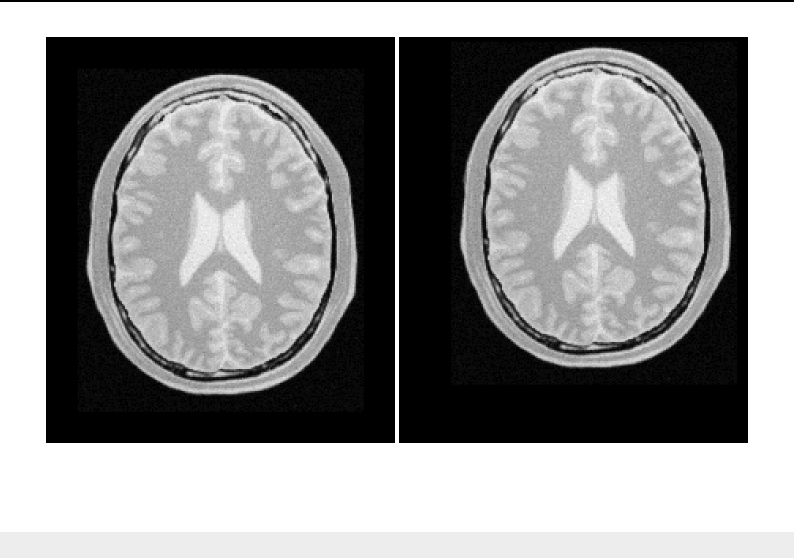

The National Library of Medicine Insight Segmentation and Registration Toolkit, shortened as the

Insight Toolkit (ITK), is an open-source software toolkit for performing registration and segmenta-

tion. Segmentation is the process of identifying and classifying data found in a digitally sampled

representation. Typically the sampled representation is an image acquired from such medical instru-

mentation as CT or MRI scanners. Registration is the task of aligning or developing correspondences

between data. For example, in the medical environment, a CT scan may be aligned with a MRI scan

in order to combine the information contained in both.